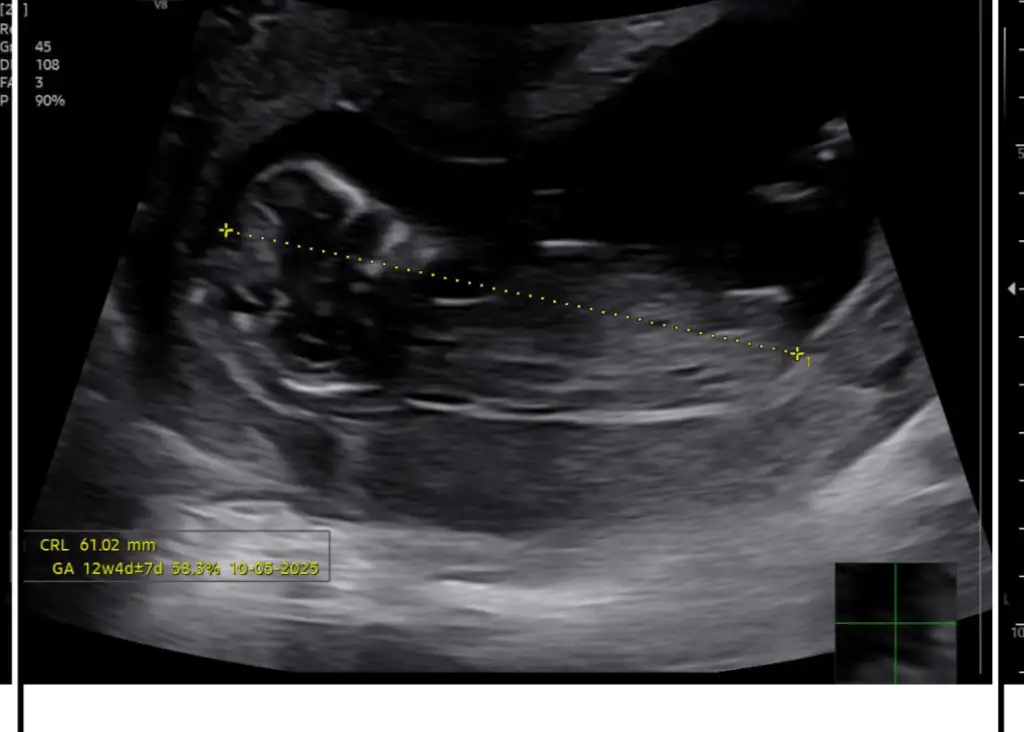

Kız canım benceBende merak ediyorum 12 haftalık tahmini olan varmı ? Eki Görüntüle 3505233

Ay inşallah bir oğlum var önce sağlıklı olsun tabi de insan olmayanı da tatmak istiyor bakalım yarın gideceğim tahminde bulunacak mi doktor ?Kız canım bence